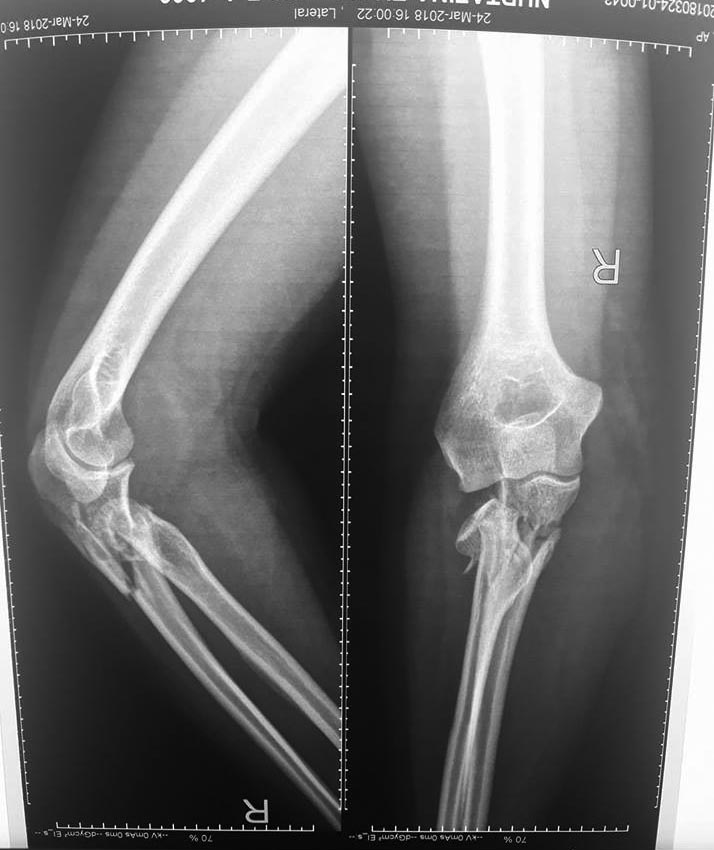

[Ortho] Повреждение проксимальных отделов radius+ulna

Добрый день, коллеги. Какие мнения будут по этому снимку?